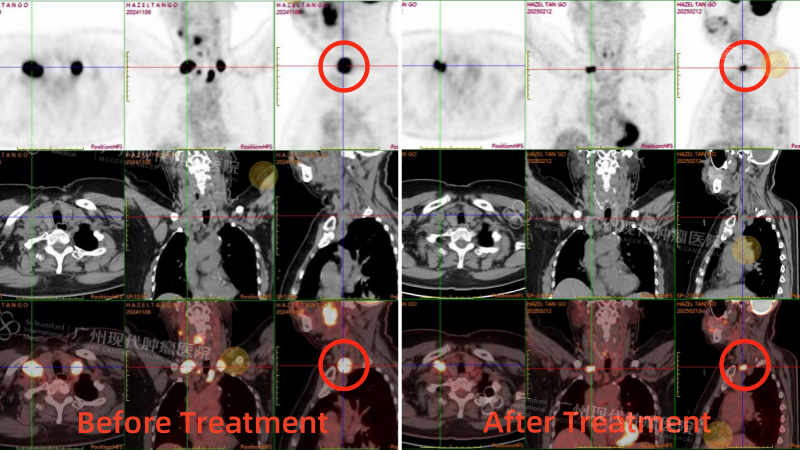

После четырёх сеансов лечения моя тётя прошла повторное ПЭТ-КТ, которое показало значительное уменьшение опухоли ротоглотки. Первоначальная опухоль размером 4,3 x 3,9 см уменьшилась до 1,7 x 1,8 см, а часть опухоли даже исчезла. Значение SUV-метаболизма снизилось с 26,4 до 7,2, что значительно снизило активность опухоли. В других метастатических зонах также наблюдалось значительное улучшение. Эти результаты были невероятно обнадеживающими. Выздоровление тёти шло на поправку. У неё не только улучшился цвет лица, вернулся аппетит, она начала набирать вес, но и стала более жизнерадостной и разговорчивой.

Сравнение результатов ПЭТКТ до и после лечения